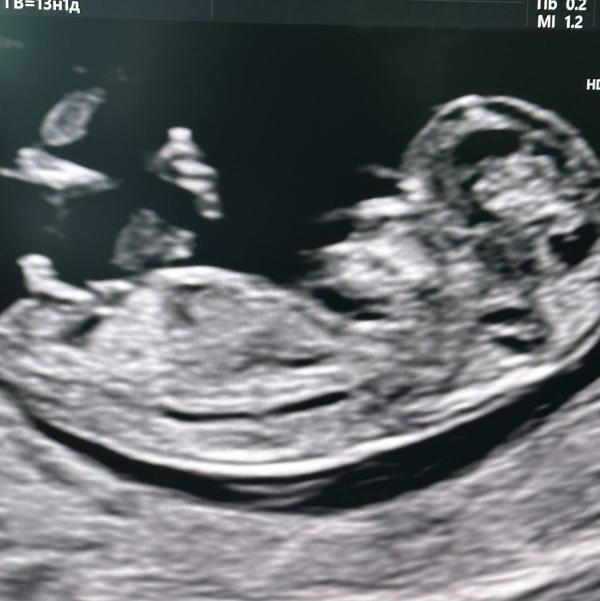

Нам подтвердили 💯 % мальчика🙃, думаю наверно анализ не нужен никакой)

у нас ещё видео 3 д снимки есть где видно отчетливо каждая частичка.

Даа, я хотела тоже проверить, думаю все тесты сдают на пол ребенка, а там всё раскрыл он и писил на узи 😄

Да мальчик